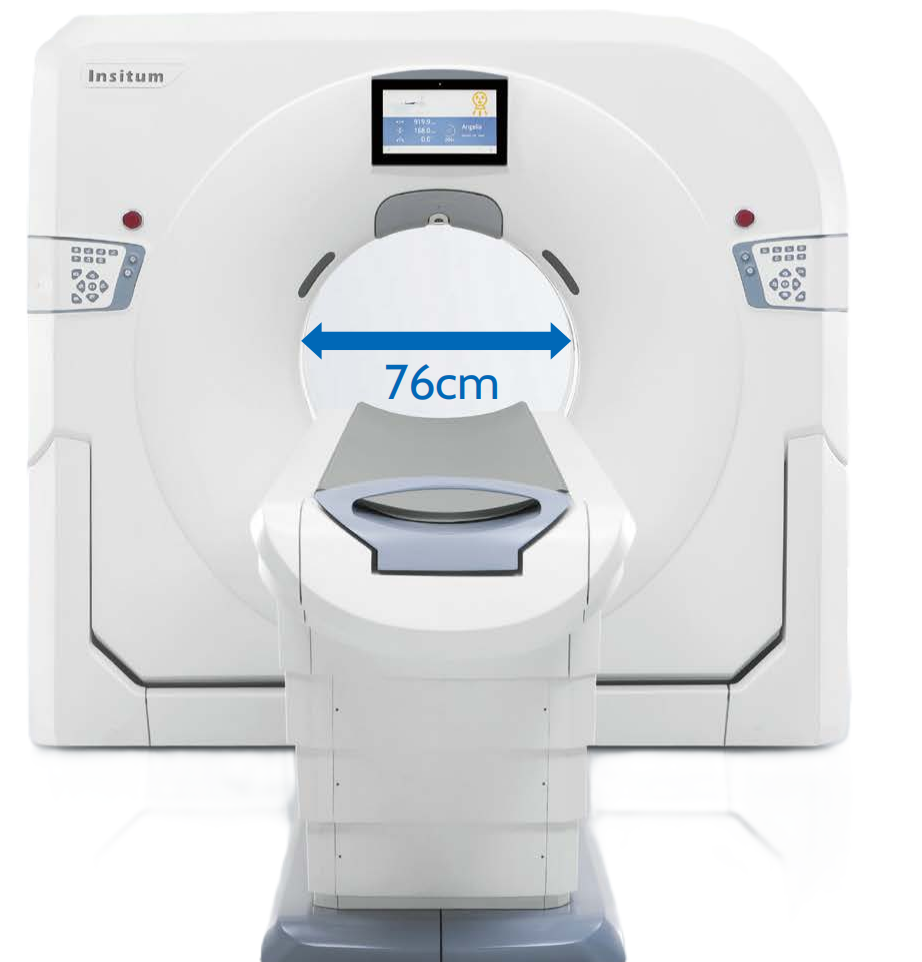

SinoVision Insitum 64s - это 64 срезовый КТ с большой апертурой гентри 75см. Один из самых доступных кардиологических компьютерных томографов. SinoVision Insitum 64 - это 64 срезовый КТ с большой апертурой гентри 76см. Уникальная интеллектуальная система управления стробированием SinoVision и алгоритм реваскуляризации коронарных артерий гарантируют мгновенное замораживание сердца и отображение структуры сердечно-сосудистой системы, стента, кальцификации, бляшек и другой информации в высоком разрешении.

Характеристики SinoVision Insitum 64

- Диаметр апертуры гентри: 76 см

Характеристики SinoVision Insitum 64S

- Диаметр апертуры гентри: 76 см